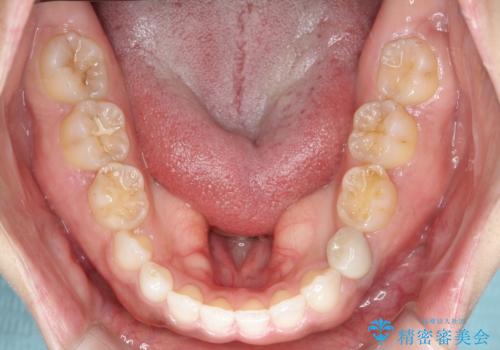

- 後続永久歯が欠損した患者様です。

矯正治療にて歯並びを改善したのち、インプラントにて咬合回復を行う治療計画としました。

捻転が強い部分だけはワイヤーの部分矯正で対応しております。